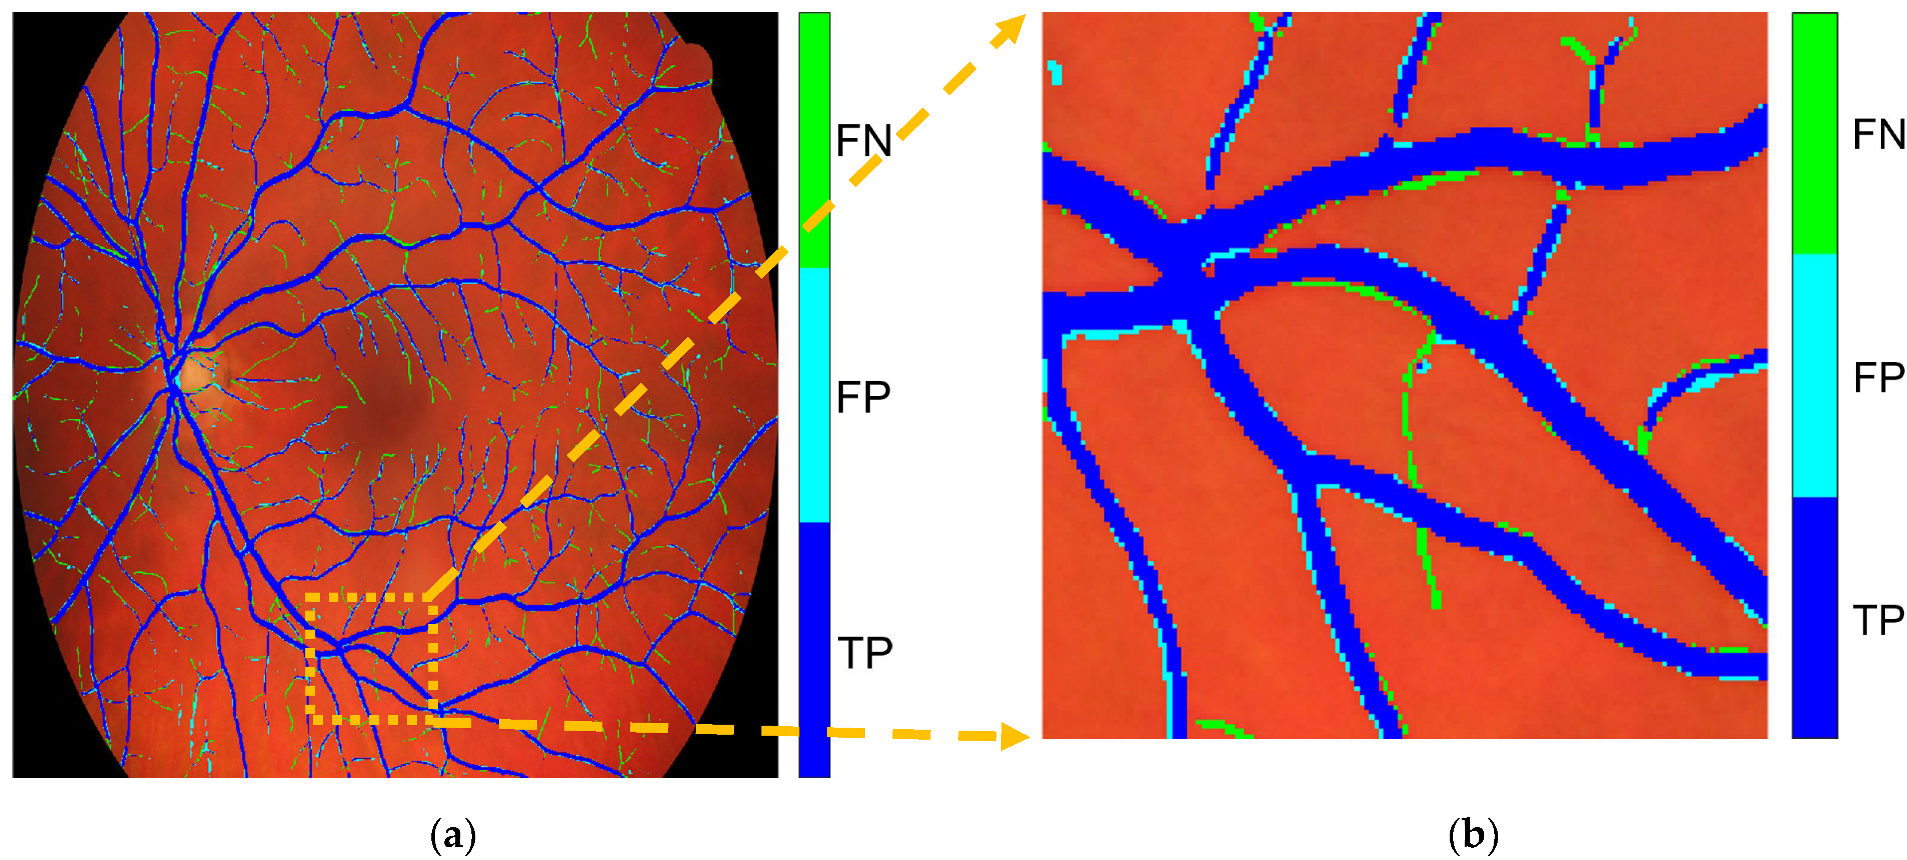

Figure 6 visualizes the segmentation results specifically for the vessel class, illustrating the relationships in the corresponding row and column of the confident joint matrix shown in Table 3. The dark blue region represents true positive (TP) pixels—those originally labeled as vessel () and also confirmed as vessel by CL (y* = vessel). This TP region contained 81,780 pixels, where the predicted probability score for the vessel class exceeded the threshold of 0.9744 indicated in Table 2. The light blue region represents false positive pixels—originally labeled as other classes but predicted by CL as a vessel. These pixels included 4 labeled as background, 14,137 as retina, and 669 as optic disc. These 14,810 pixels exceeded the vessel threshold of 0.9744 but fell below the thresholds of their putative classes, indicating potential label noise. Conversely, the light green region represents false negative pixels—originally labeled as vessel but identified by CL as other classes. This group included 1 pixel now reclassified as background, 16,686 as retina, 1 as fovea, and 615 as optic disc. For these 17,303 pixels, the thresholds of their reclassifications exceeded the probability threshold for the vessel classification, suggesting mislabeling in the original annotation.

The confident joint matrix shows for image im0001 shows 5981 false-positive pixels misclassified as background and 23,960 as a vessel. These values reflect the labeling discrepancies identified by the CL method and are visualized in the observed issue mask shown in Figure 7a.

To prioritize these potentially mislabeled pixels, the normalized margin, as defined in Equation (4), was applied to all pixels in the observed issue mask. Each pixel was then ranked in ascending order by its normalized margin score, where a lower score indicated higher uncertainty and a greater likelihood of being mislabeled.

To evaluate the effectiveness of CL in detecting label errors, PBNR was used to examine the overlap between Figure 7a (the observed issue mask) and Figure 7b (the true issue mask). Pixels present in both masks were classified as true positives (TPs) and highlighted in Figure 7c. Additional categories—false positives (FPs), false negatives (FNs), and true negatives (TNs)—were also represented in Figure 7c and summarized in Table 6. An FP refers to a pixel present in Figure 7a but not in Figure 7b, indicating an incorrectly flagged error. An FN refers to a pixel present in Figure 7b but absent from Figure 7a, representing an error missed by CL. A TN refers to a pixel not flagged by CL in Figure 7a and correctly labeled according to the ground truth, which is an appropriate case of no error detected.

Table 7 lists the top 10 candidate label errors in im0001, ranked by their normalized margin scores. Here, the “true label” refers to the VK ground truth annotation, while the “true issue” column indicates whether each candidate was a confirmed labeling error (one) or not (zero), based on a comparison with the true issue mask derived from annotation disagreements between AH and VK (Figure 7b).